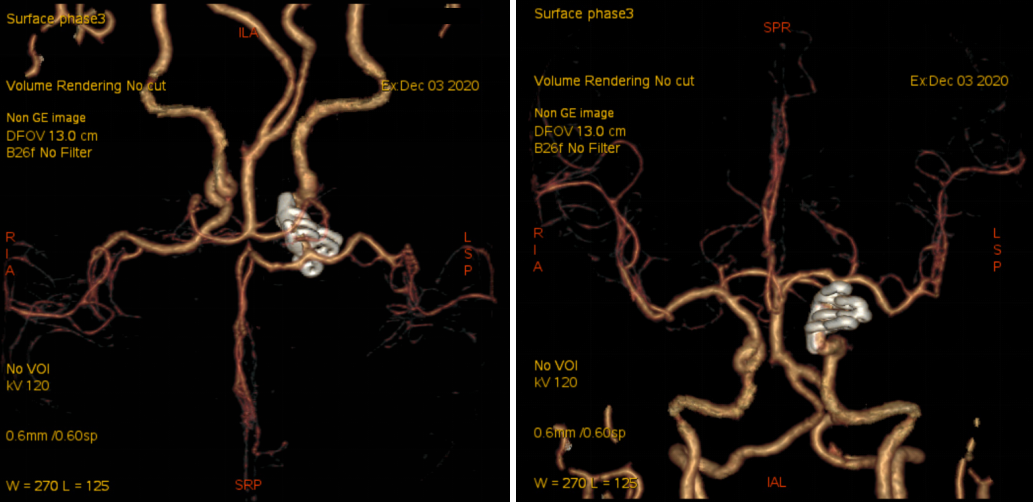

入院后予完善MRI及头颅DSA检查提示右侧颈内动脉眼动脉段动脉瘤;告知其介入栓塞、开颅夹闭等治疗方式、利弊、风险及费用等,患方商量后决定行开颅动脉瘤夹闭术。

科内讨论后认为:患者颈内动脉床突旁大动脉瘤诊断明确,患者动脉瘤破裂出血,需急诊手术治疗。术中应先在颈部暴露颈内动脉。采用Dolenc入路硬膜外磨除前床突及视神经管。术中注意保护好眼动脉。暴露动脉瘤后可孤立动脉瘤,并在颈部穿刺颈动脉并逆向抽吸,降低动脉瘤的张力后塑形夹闭动脉瘤。

患者术后病情稳定,神清,语明,双侧瞳孔等大等圆,直径约2.5mm,光反应灵敏,视力及视野正常,四肢肌力、肌张力正常。